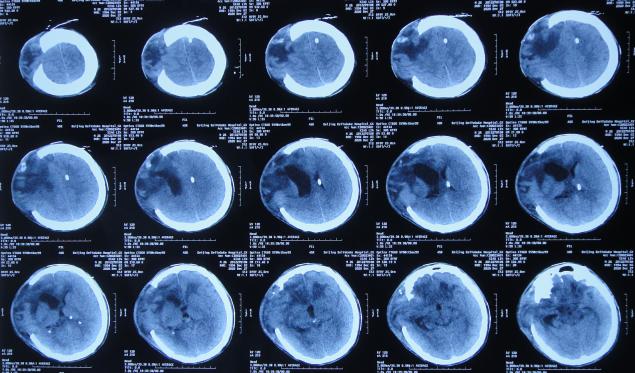

开颅术后9天即2020年12月21日,查头颅CT示有好转( 图-4 )。

图-4: 2020年12月21日头颅CT